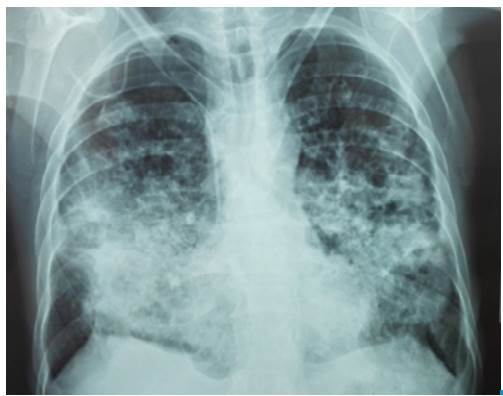

The patient visited a primary health center referring symptoms of 4 months evolution including productive cough with mucopurulent expectoration, progressive dyspnea even when putting small efforts, fever, chills and unintentional progressive weight loss. He stated that the symptoms exacerbated 7 days before with hemoptoic cough and evening diaphoresis. The patient was referred to a secondary care health center where a chest x-ray was performed, showing abundant alveolar opacities in both pulmonary fields, formation of diffuse pneumatoceles, and signs of air trapping (Figure 1). A sputum KOH test was performed, reporting a double refractory wall of yeast with intracytoplasmic vacuoles with multiple or chain budding. The results were compatible with paracoccidioides, so he was assessed by the internal medicine service and referred to the Hospital Universitario de Santander due to the high risk of ventilatory failure.

Chest x-ray with abundant alveolar opacities in both lung fields with formation of pneumatoceles.

Figure 1: Chest x-ray with abundant alveolar opacities in both lung fields with formation of pneumatoceles.

Chest scans are the main tool to suspect this infection. Findings are nonspecific and include diffuse micronodular infiltrates predominantly in the middle zone of the lung, cavitations and tumor masses 5,14,15. Chest radiography shows mainly interstitial opacities (nodular or reticular), and when caverns are observed, pulmonary tuberculosis is the main differential diagnosis. 15,16. In high-resolution chest tomography, untreated PCM findings are characterized by attenuation of the ground-glass lung parenchyma associated with small centrilobular nodules, cavity nodules, large nodules, and scar emphysema 5,15,16, being the peripheral and the posterior distributions in the lung predominant 16. The reversed halo sign is observed in about 10% of cases 16.